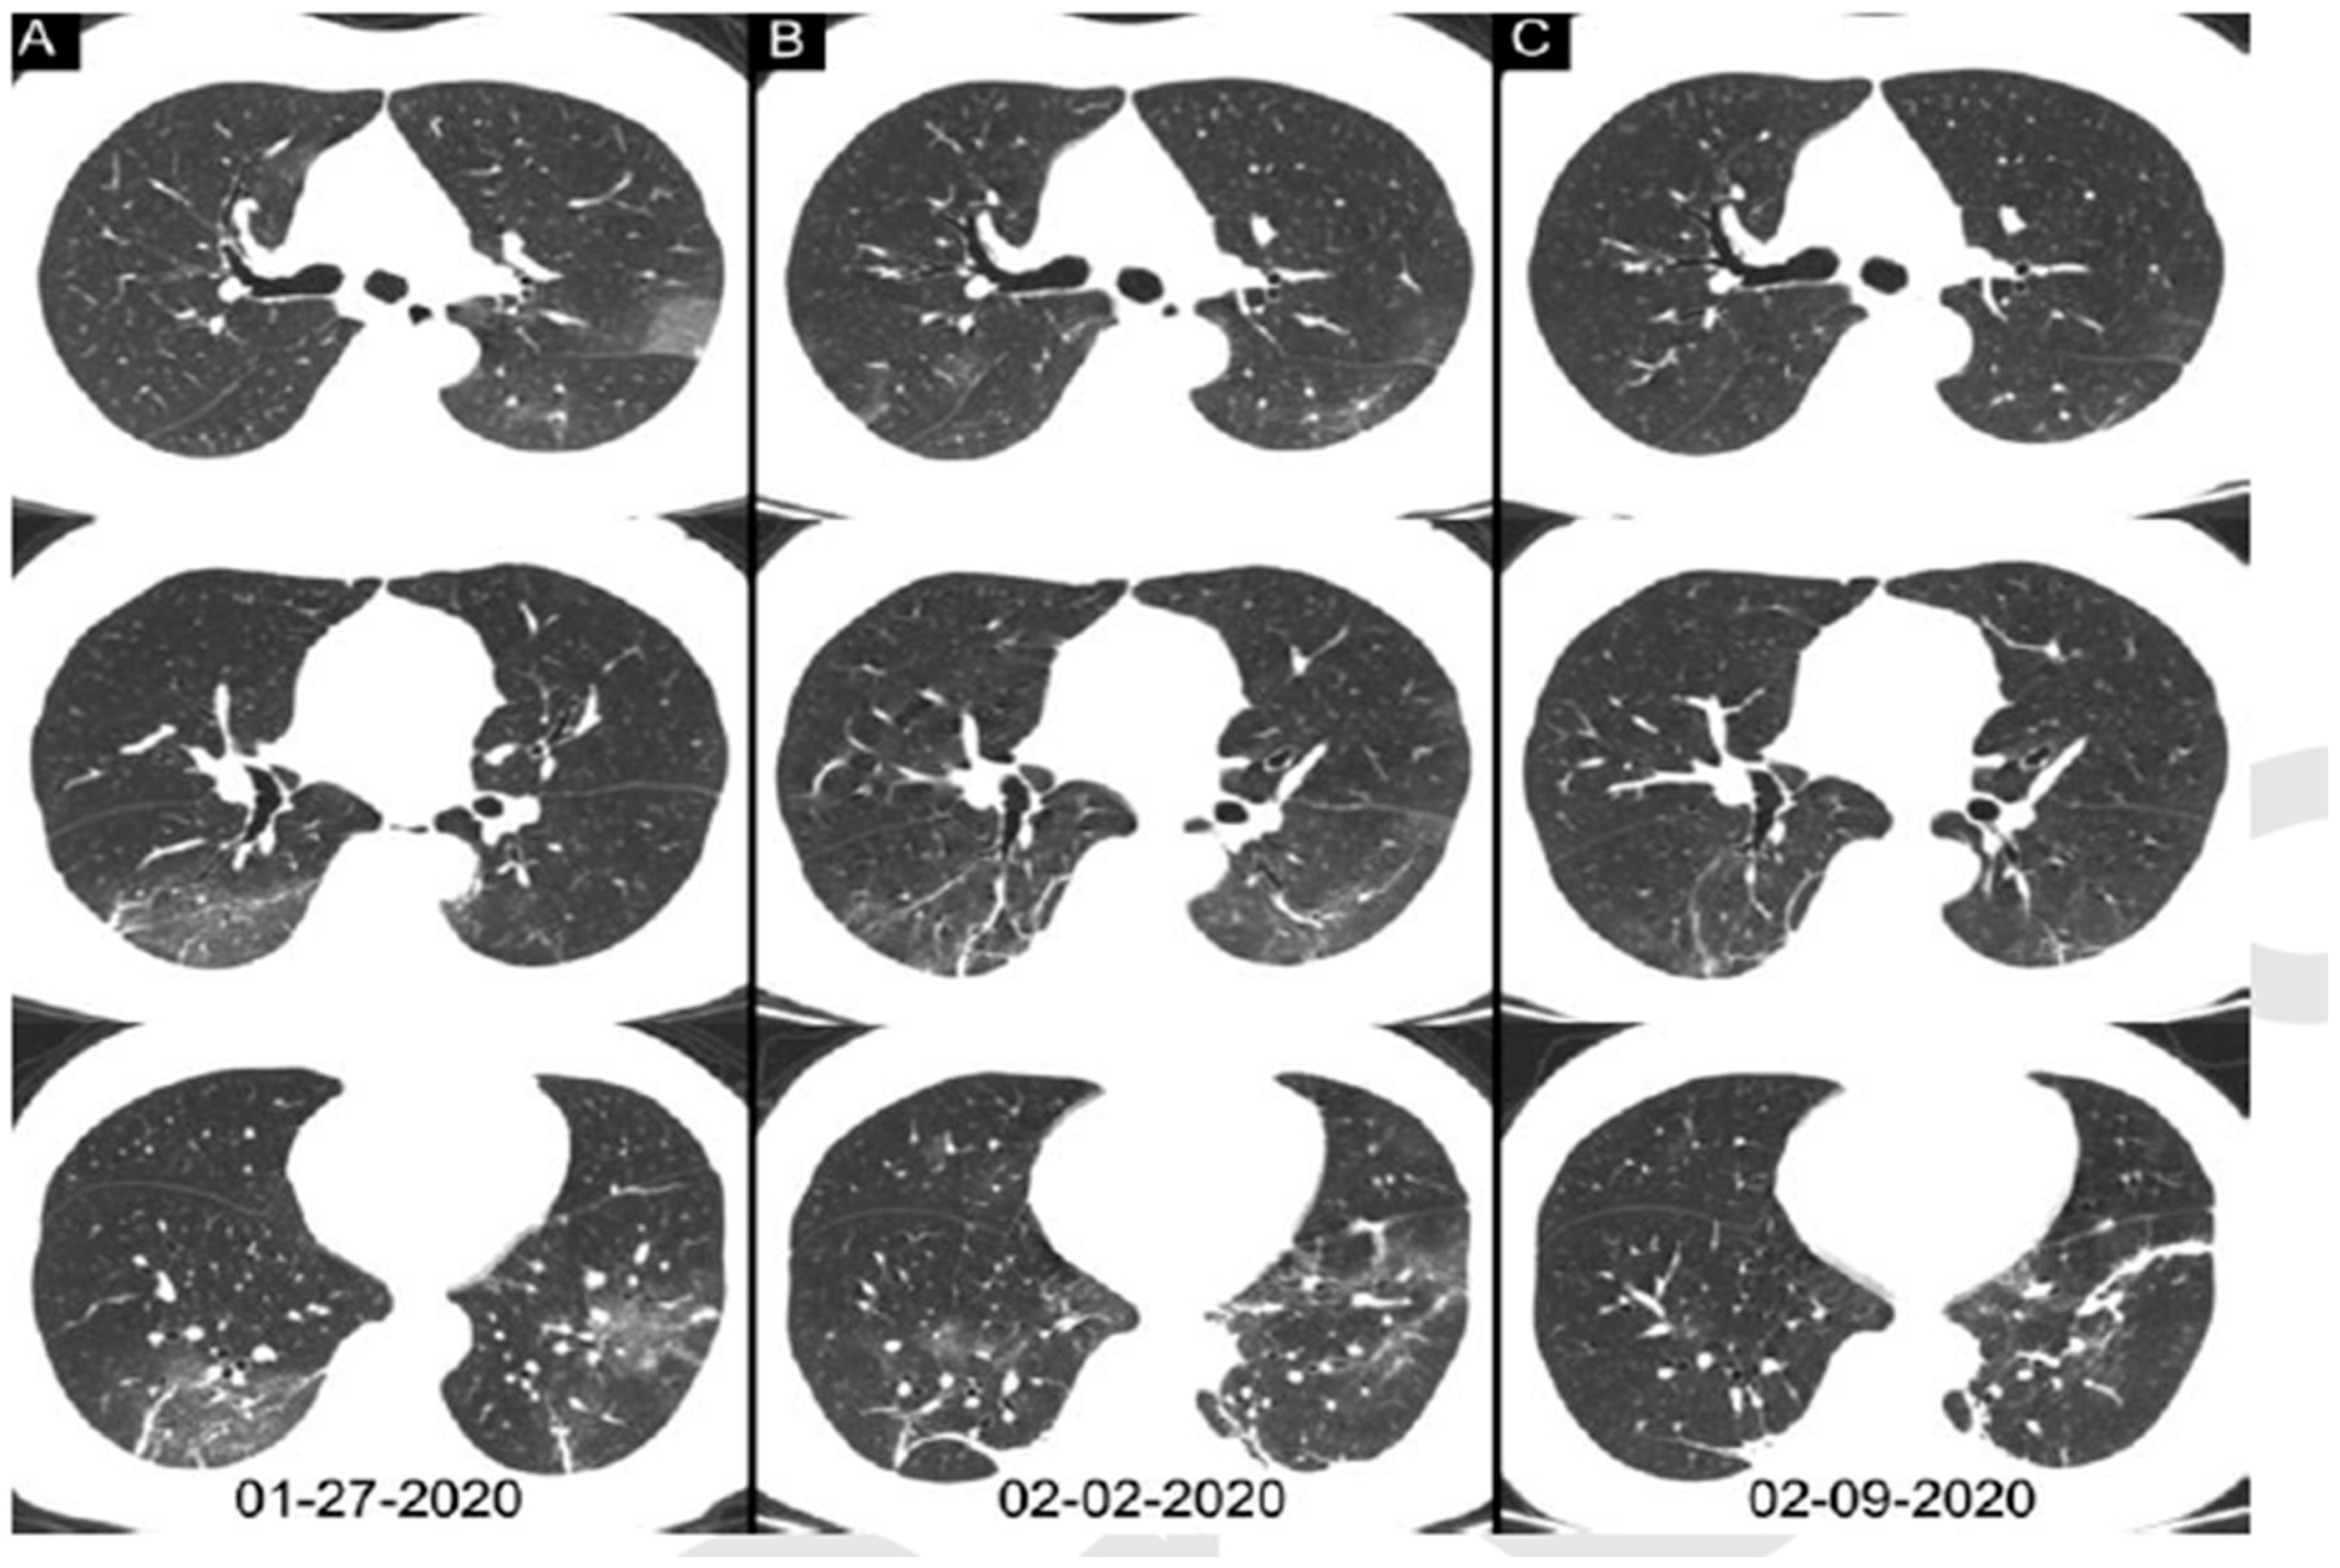

Compare COVID Presentation in CT and CXR and others Viruses